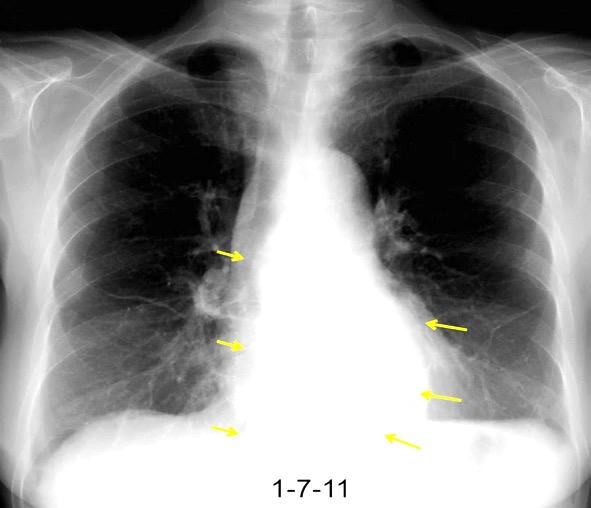

Ganglios retroperitoneales (flechas negras)

germinales del testículo izquierdo Nódulos pulmonares múltiples. (flechas verdes). Ganglios paratraqueales. (flechas amarillas). Dudoso ensanchamiento retrocrural (flechas negras)

Panda A et al. “Straddling Across Boundaries”. Thoracoabdominal Lesions: Spectrum and Pattern Approach. Curr Probl Diagn Radiol, 2015